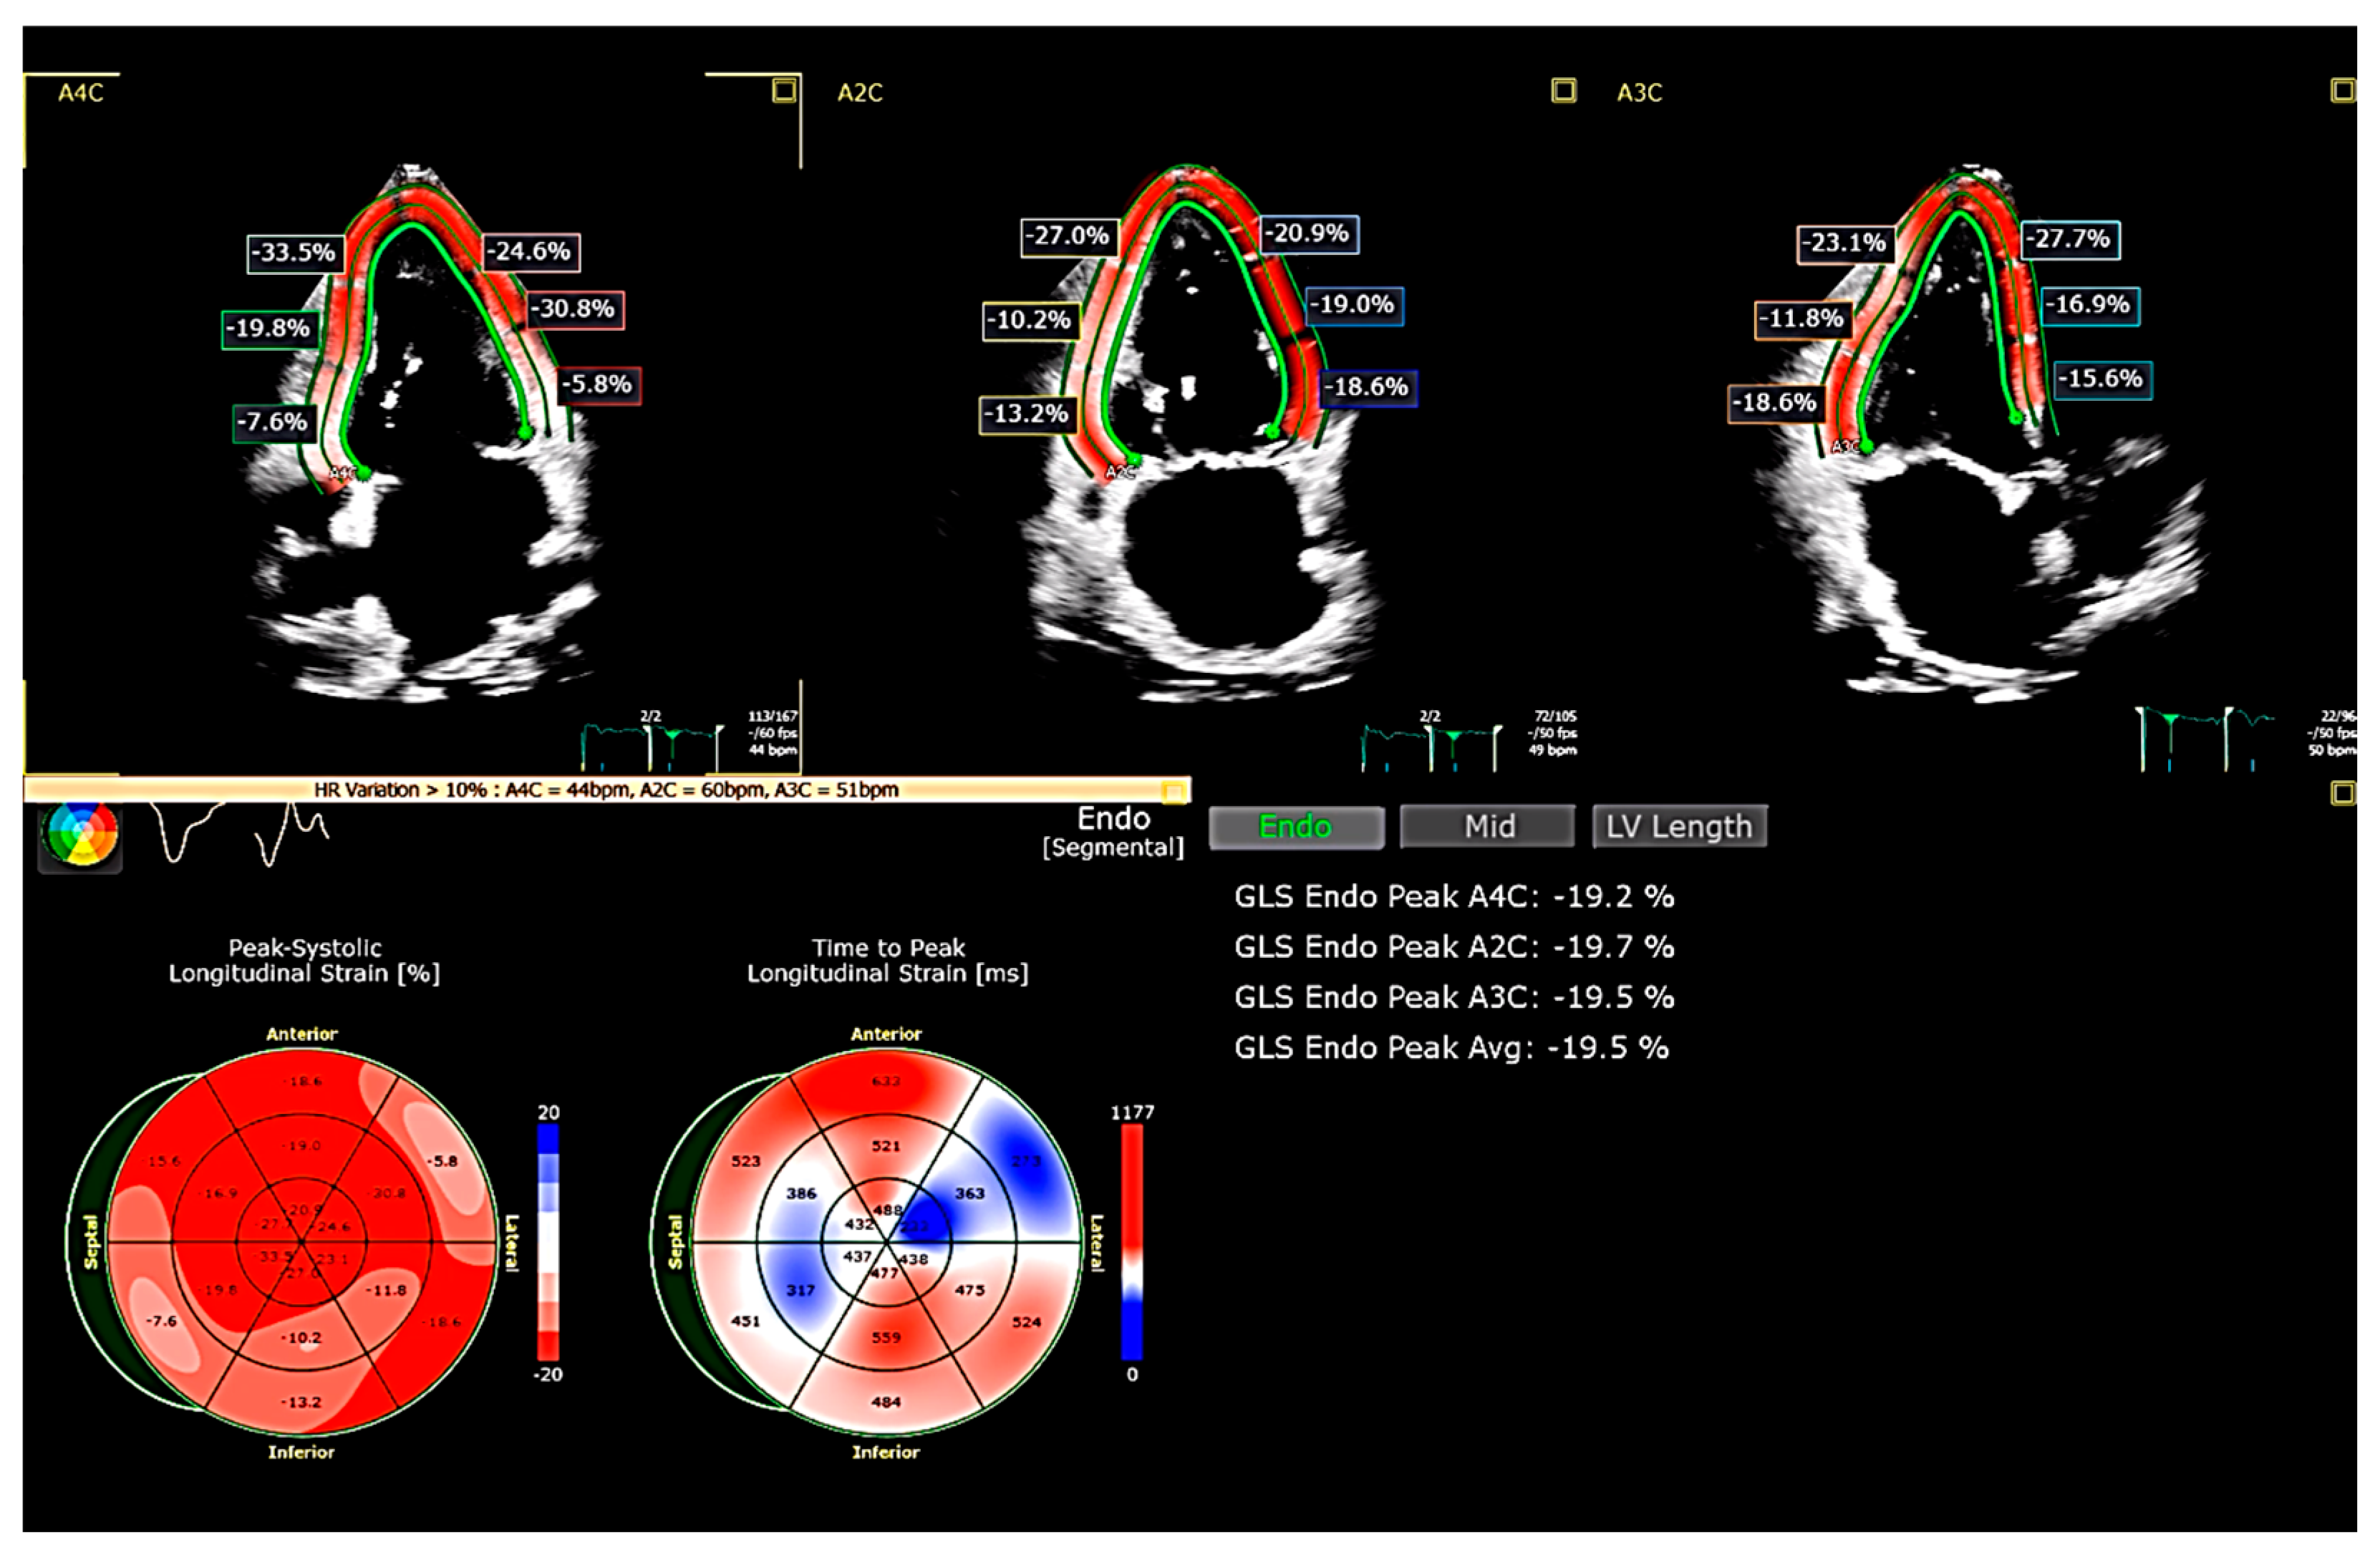

2. Limitations in the Diagnosis of HFpEF

3. Global Longitudinal Strain (GLS)